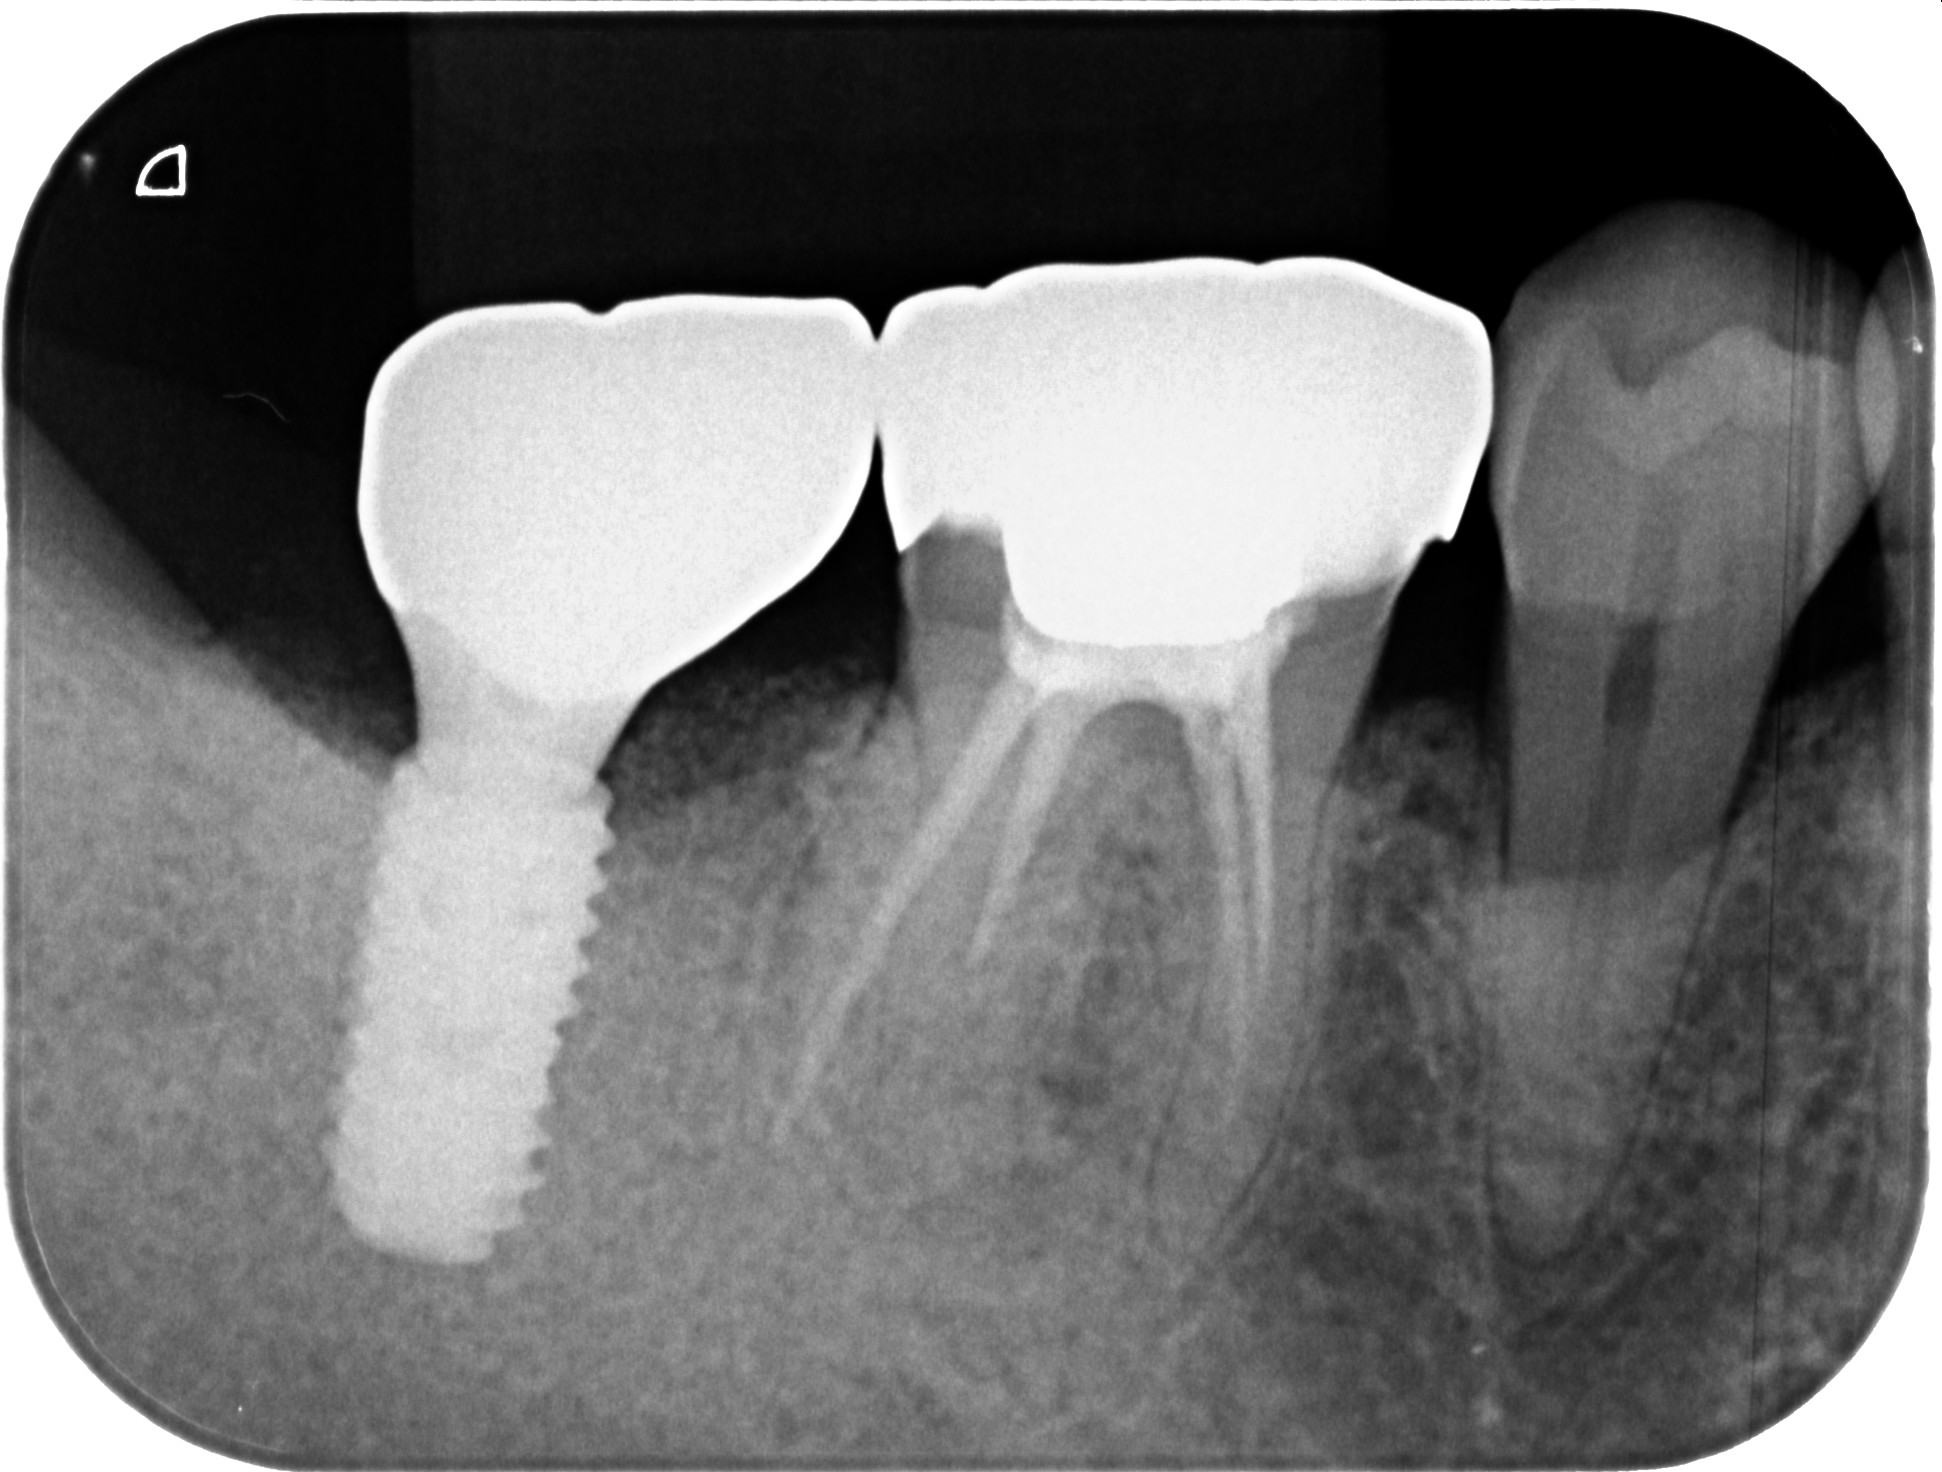

インプラント後、最終的な被せ物(ジルコニア)装着後のエックス線

上部構造(ジルコニア):スクリュー固定